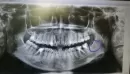

У меня на месте 8-ки или дальше неё есть твёрдое образование. Будто лезет зуб внутрь, в сторону языка, но зубы мудрости у меня уже выросли и их удалили. Раньше слева было просто твердое. А на днях начала болеть вся левая десна, а в том месте как острие появилось. При нажатии болит, но не сильно. И с правой стороны тоже есть чуть припухлость твердая, но гораздо меньше. Еще с апреля прошлого года у меня зубы стали сами сильно смещаться и даже чуть поворачиваться.

На этом снимке не определяется ничего необычного в обведенной области. Скученность могли вызвать зачатки восьмых зубов, патология окклюзии, вредные привычки. Вам необходимо обратиться к стоматологу-ортодонту для диагностики.